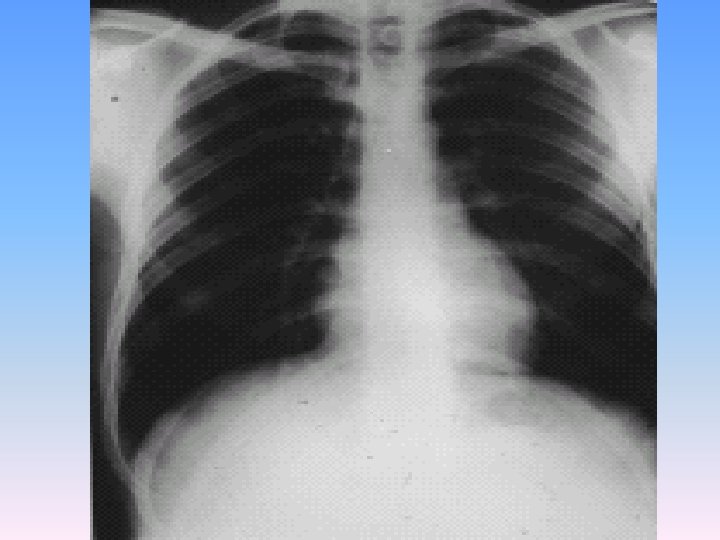

Physical Exam § A well being girl with no distress. Vital signs were stable. No fever. § Sclera was icteric with mild anemia. § Chest & heart were normal. § There was a mass in RUQ in inspection. § Tenderness in RUQ without morphy sign. § An ill defined mass was detected in RUQ in palpation which does not move with respiration. § It was palpated about 5 cm below right costal margin. § Spleen was normal. No ascitis was detected.